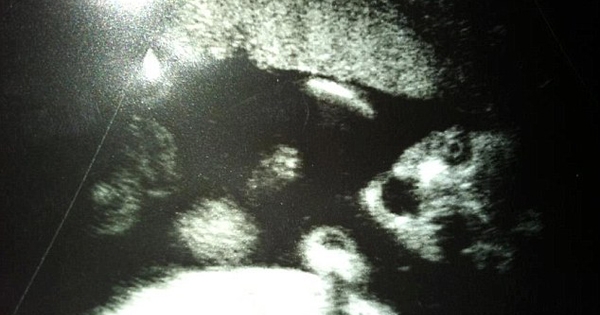

当妈妈真是一件让人兴奋的事,每个妈妈最期待最好奇的就是看一眼肚子里的宝宝,无时无刻都想看看他们可爱的模样。可是,当每个充满期待妈妈看到肚子…